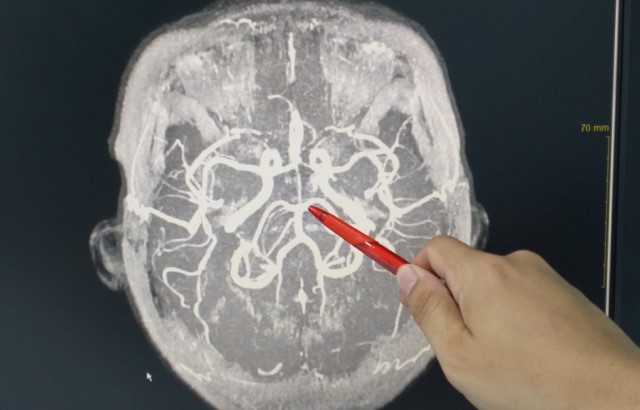

High blood pressure is a main cause of vascular dementia, a condition characterised by poor blood flow to the brain. The reduced blood supply starves brain cells of nutrients and over time they become damaged and die. Symptoms of vascular dementia include loss of energy, lack of concentration and poor memory.

It's normal for the brain’s arteries to narrow and widen in response to changes in blood pressure. However, consistently high blood pressure causes arteries to stay narrow and restrict the brain’s blood supply. Until now, it was not known how.

The study, from researchers at the Geoffrey Jefferson Brain Research Centre at The University of Manchester, reveals that – in mice – high blood pressure disrupts messaging within artery cells in the brain. They found that this occurs when two cell structures, that normally help transmit messages that tell arteries to dilate, move further apart. This stops the messages reaching their target, which causes the arteries to remain permanently constricted, limiting blood flow to the brain.